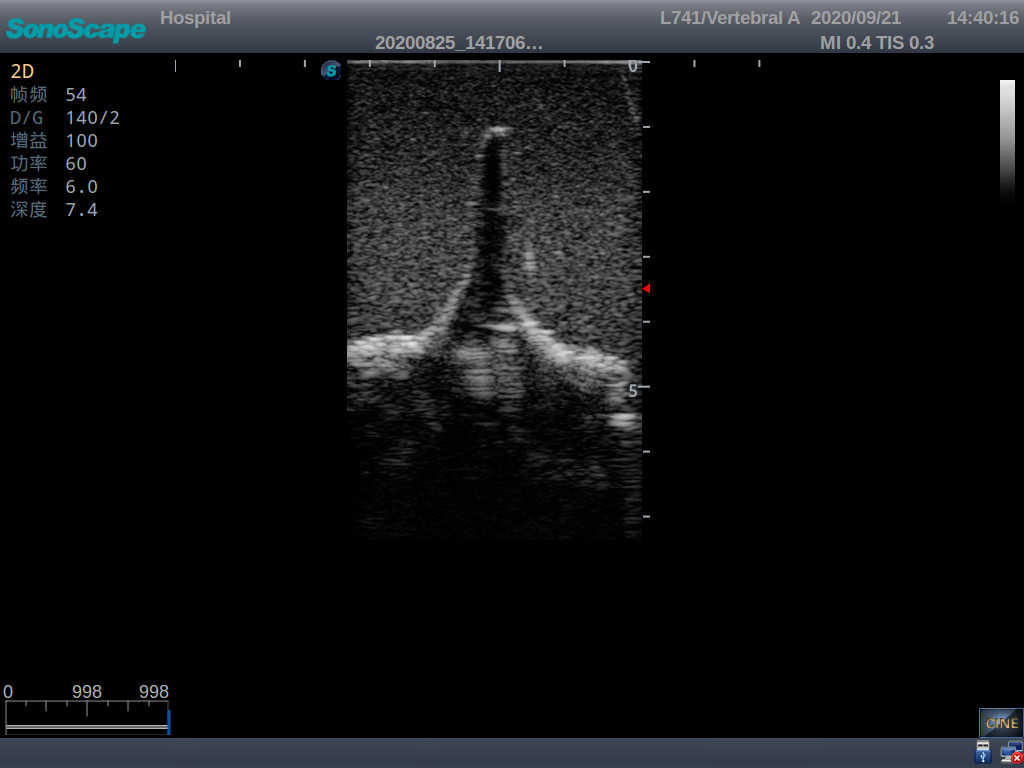

Adult Lumbar Puncture Ultrasound Training Model

Model TYE1549.2

Outline

This model is an ideal choice for ultrasound-guided adult lumbar puncture training with true-to-life skin feel and touch, accurate anatomical structures as well as real clinical ultrasound images. Realistic resistance to needle tips and correct landmarks provide excellent hands-on experience.

Accurate anatomical structure of L1-L5 and the vertebral canal

2)  Real clinical ultrasound images

1)   Ultrasound-guided lumbar puncture practice